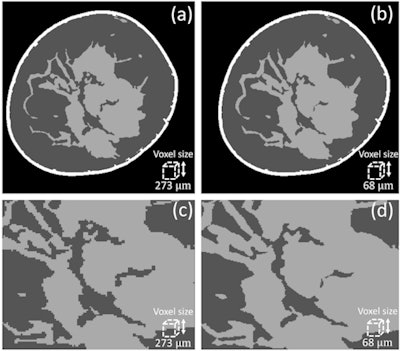

Sechopoulos and colleagues acquired images using a clinical breast CT system with a nominal pixel size of 194 µm and reconstructed with a voxel size of 273 µm. Aiming to increase the phantom resolution by a factor of four from the patient image, their first step was to reduce the voxel size in the clinical image from 273 µm to 68 µm.

Simply reducing voxel size, however, does not recover fine glandular details. Instead, first author Marco Caballo, a doctoral student at RUMC, used a machine learning-based regression algorithm to calculate the glandularity at the original resolution, the expected glandularity at 68 µm and the estimated glandular tissue loss. They then employed a second algorithm -- a convolutional neural network -- to iteratively recover glandular details by mapping between low- and high-resolution images until reaching the predicted glandularity. (Physics in Medicine & Biology, 13 November 2018, Vol. 63:22)

To evaluate their proposed method, the researchers used 10 clinical breast CT images (reconstructed at 273 µm) to generate superresolution phantoms with 68 µm voxels. They then downsampled these phantoms back to 273 µm. Comparing calculated glandularity values between the downsampled super-resolution phantoms and original breast CT images resulted in an average error of 0.27%.